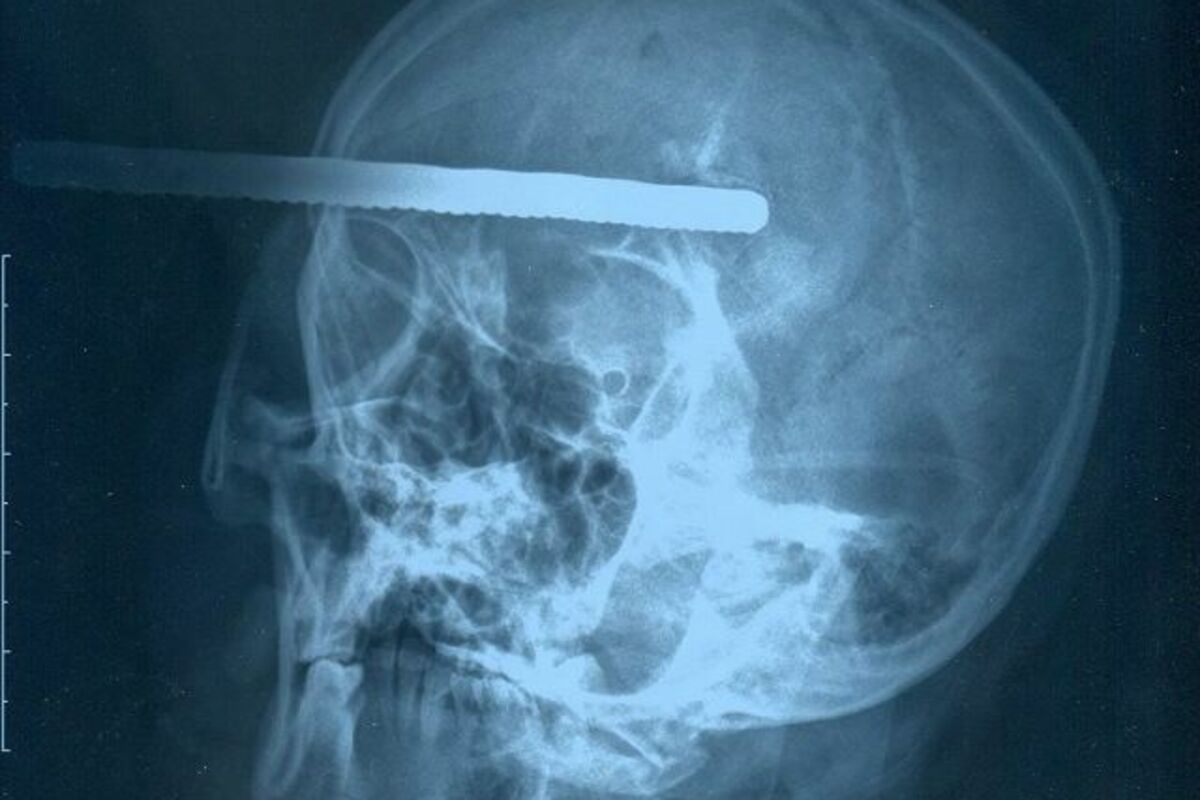

Radnica na građevini preživjela je zastrašujuću povredu nakon nesreće tokom koje se metalna šipka zarila duboko u njenu lobanju.

Čeng Fengua (48) iz Ankving u provinciji Anhui, istočna Kina, imala je hitnu operaciju nakon što je šipka prodrla 8 centimetara u njenu glavu, piše Dejli Mejl.

Gospođica Čeng radila je na zgradi kad je metalna šipka duga 4 metra pala sa krova. Jedan od svjedoka kaže da je vidio dugačku crnu stvar kako pada sa visine a onda je čuo vrisak.

"Kad sam pogledao iz blizine bio sam šokiran jer je dugačka čelična šipka virila iz lobanje", rekao je.

Njene kolege su pozvale hitnu pomoć i upotrijebili alat da skrate šipku na 20 centimetara da bi Čeng mogla da bude odvedena u bolnicu. Rendgen je pokazao da je šipka bila 8 centimetara u mozgu gospođice Čeng.

Hirurzi su bili u mogućnosti da uklone šipku i Čeng je sad u ozbiljnom, ali ne i po životom opasnom stanju. Dr Jang Jocong je rekao da je oporavak gospođice Čeng bio nevjerovatan.

"Da je ušla samo malo dublje pacijent bi umro istog trenutka", rekao je.